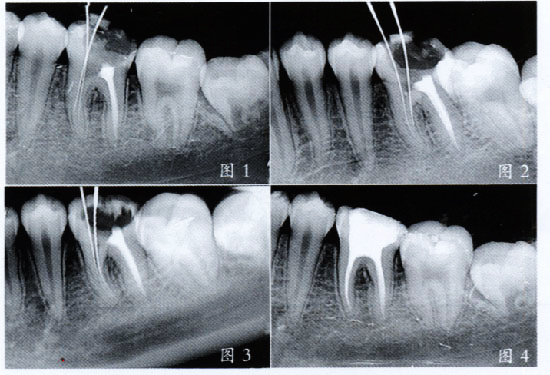

完善牙髓治疗

残留的牙根经过治疗后进行全瓷冠修复